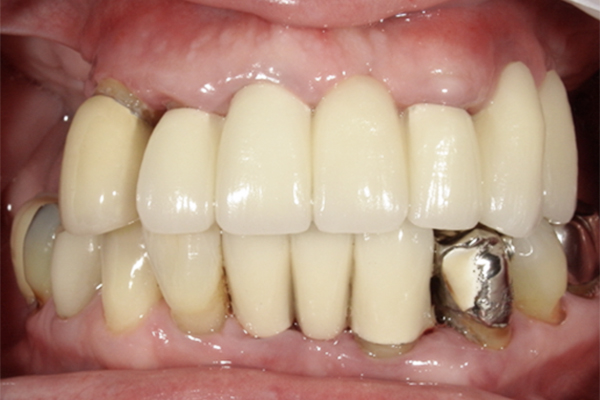

| 主訴 | 奥歯で噛めない、顎が痛い |

|---|---|

| 治療内容 | 奥歯のインプラント治療、前歯・奥歯の被せ物治療 |

| 治療期間 | 6ヶ月 |

| 治療費 | 350万円 |

| 治療リスク | 被せ物をつけた初期の段階で歯がしみることがある(時間とともに改善する) インプラント治療後に3日程度痛みと腫れを伴うことがある |